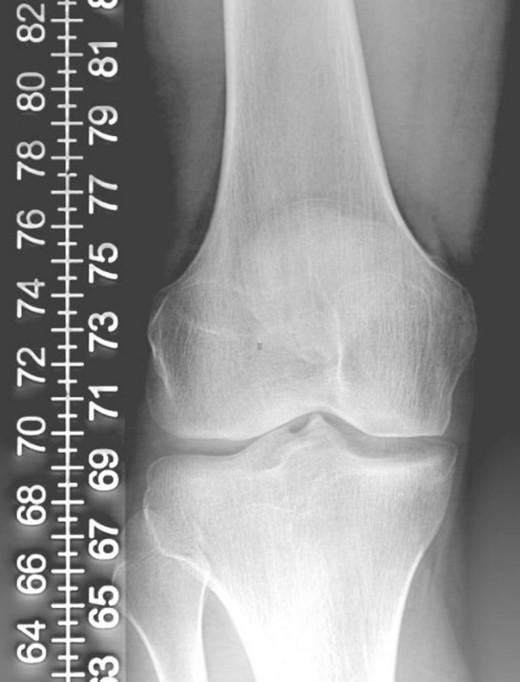

A 23-year-old male veterinarian presented to our out-patient department postright ACL reconstruction with hamstring autograft, PHMM tear by all-inside repair via sMCL pie-crusting technique, and lateral extra-articular tenodesis (modified Lemaire) in June 2023. A preoperative plain radiograph of the right knee revealed no evidence of HO (Fig. 1). No evidence of heterotopic ossification was detected in the right knee on plain radiographs taken 2 weeks postsurgery. (Fig. 2). Five months postsurgery, plain radiographs revealed new bone formation at the medial femoral condyle, precisely where the sMCL femoral origin was located (Fig. 3). The patient was asymptomatic and continued with rehabilitation. Seven months after the surgery, the patient started to complain of pain and clicking sensations when the right knee was flexed beyond an angle of 130°. Magnetic resonance imaging revealed consolidation of the newly formed bone, leading to a diagnosis of HO post-sMCL pie-crusting (Fig. 4). Nine months following surgery, the patient began to feel a bony mass on the medial side of the right knee. A plain radiograph and computed tomography (CT) scan revealed the complete formation of a bone island (Fig. 5). The past surgical history of this patient revealed that he had undergone left knee ACL reconstruction with hamstring autograft in December 2021, which failed and was complicated by a PHMM tear. The patient had presented to our facility for a revision. A revision ACL reconstruction was done using a bone-tendon-bone (BTB) autograft and PHMM tear all-inside repair via the sMCL pie-crusting technique in February 2022. A 2-year follow-up of the left knee, including physical examination and 3D-CT scans (Fig. 6), revealed no symptoms or signs of HO, although the same technique of sMCL pie-crusting was employed. Our patient suffered no head trauma during treatment. Past medical, drug, allergy, family, social histories, and reviews of systems were irrelevant to our case.

Plain radiograph of right knee AP (A) and lateral (B) 2 weeks postoperative showing no HO.